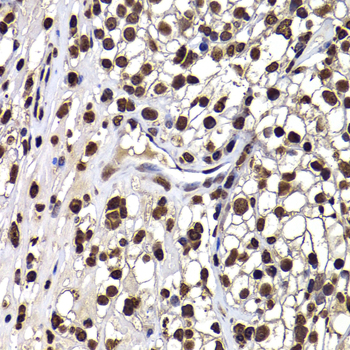

Immunohistochemistry of paraffin-embedded human kidney using DNAJB6 antibody at dilution of 1:100 (x400 lens).